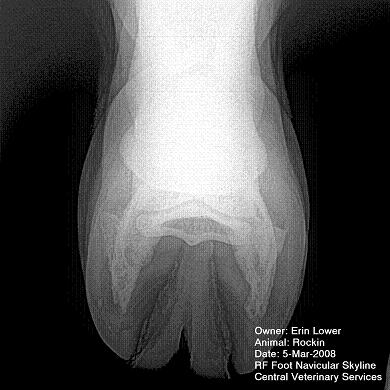

So, Rockin's x-rays were sent to a radiologist and he confirmed "normal" changes in the navicular bones for a horse her age, but slightly more significant ones in the right (sore) foot.

She also has sidebone in both fronts, but apparently that isn't causing any discomfort.

Finally, she has a "small chronic exostosis on the lateral aspect of the proximal phalanx" which, according to the radiologist, shouldn't be causing discomfort but I have read that these can be mild-to-moderately painful... I wouldn't mind another opinion on that.

I will attach as many images as possible from her x-rays (there are many different views). I don't have any pics of the feet as someone deleted them from my camera before I could download them. I'll try to take pics next time she is trimmed. Please, anyone with knowledge of hooves, give any opinions that you might have (especially Dr. O!)

Hello Erin and welcome back,

I cannot rule out lesions based on these images but I will take your radiologist's word that he does not see significant lesions. The exostosis on the RF would be above the level of a well conducted PDN which I believed blocked the lameness before?